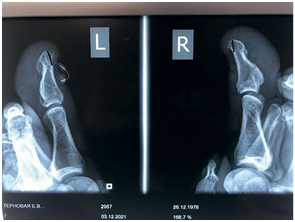

На этом снимке отчетливо виден экзостоз

Клиент обратился с проблемой отрастания здорового ногтя, был отправлен на консультацию к хирургу на предмет экзостоза. Диагноз подтвердился, была проведена операция, и спустя месяц клиент обратился к нам за помощью в отращивании здоровой ногтевой пластины